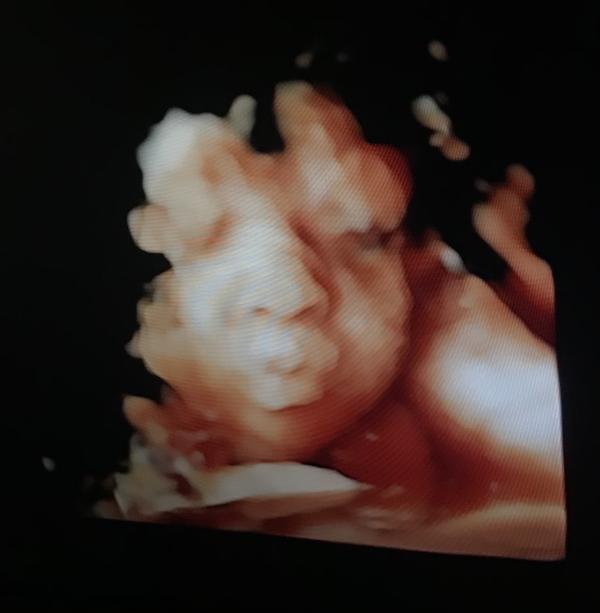

Сегодня ездили с мужем на скрининг. Все хорошо, вес малышки 2100, однократное обвитие.

Наша маленькая бусинка 😌🧁